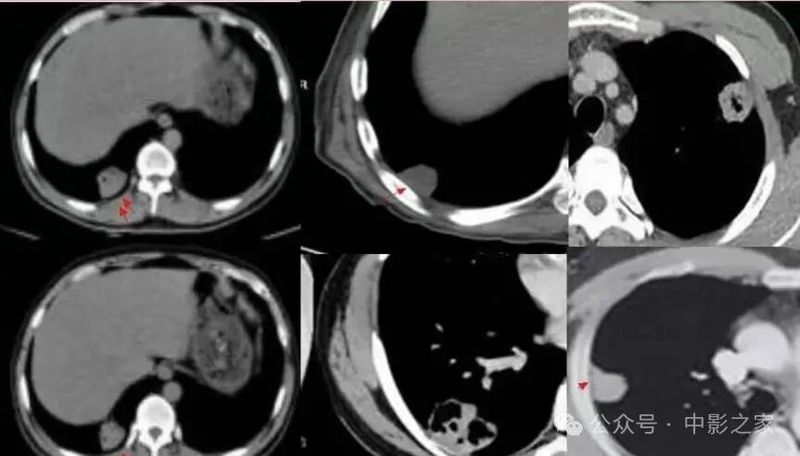

一、结节肿块型

1、部位:一般位于胸膜下,背侧胸膜下为主,两下肺明显,上肺偏少(3/4位于下叶 )

肺泡巨噬细胞吞噬肺隐球菌后根植于肺循环末梢血流缓慢或停滞处的肺外周带。

2、与胸膜关系:2/3与胸膜之间有空隙,1/3与胸膜相连,表现为糊墙征(附近胸膜增厚、胸膜外脂肪间隙增宽)

3、大小:结节较小,多为2cm以下;

4、边缘:绝大部分边界清楚,边缘可见平直征、刀切征,可以有细小毛刺,比较纤细,多为晕征中毛刺,相对收缩力偏弱;少数病人收缩比较明显

5、密度及强化:实性部分密度均匀,约1/3内部可见空泡征、实变中的空洞或空腔(可以单个内壁光滑,也可以多分隔)、含气支气管征;增强后均匀强化(强化轻到中度)延迟强化;

6、与血管的关系:2/3近端与血管相连,部分血管自然穿过;

7、晕征:1/3有晕征,晕多范围较小,个别晕较大。